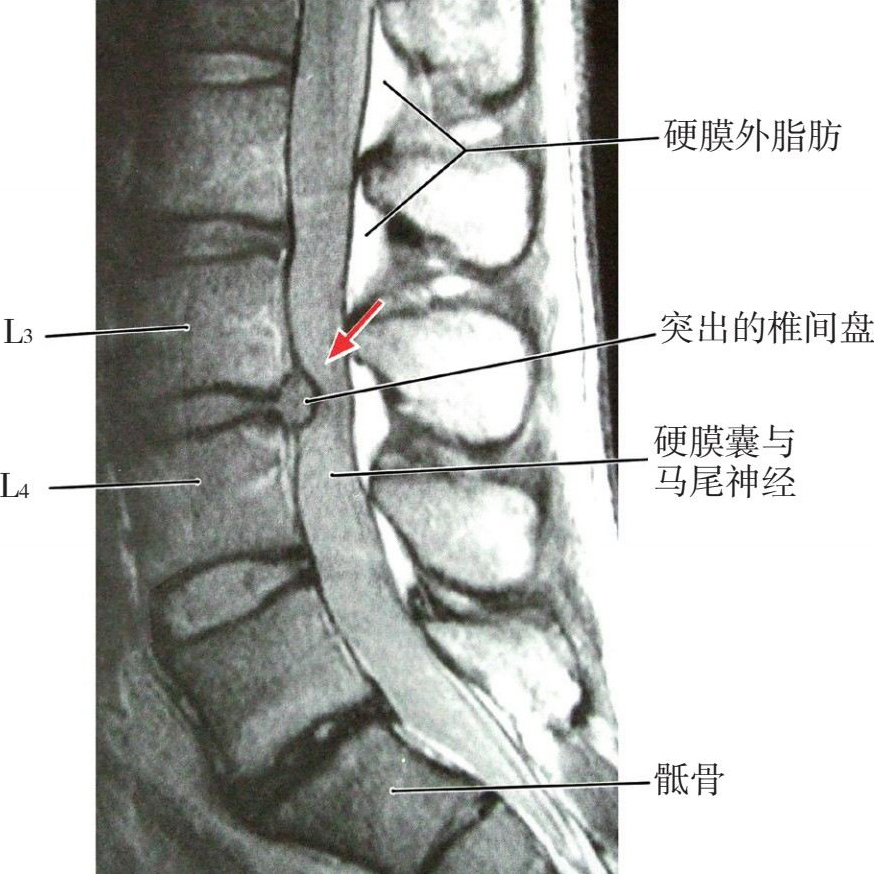

【应用解剖】

图4-29 L 3 、L 4 之间椎间盘突出

腰椎间盘突出症乃由于急性外伤或反复多次劳损引起腰椎间盘纤维环破损、髓核脱出、神经根受压所致(图4-29至图4-32)。腰椎间盘突出部位的纤维环、韧带、关节囊或神经根等产生无菌性炎症、充血、水肿刺激神经末梢引起疼痛。硬膜外封闭疗法有抑制神经末梢的兴奋、改善局部血运、消除炎症的作用。